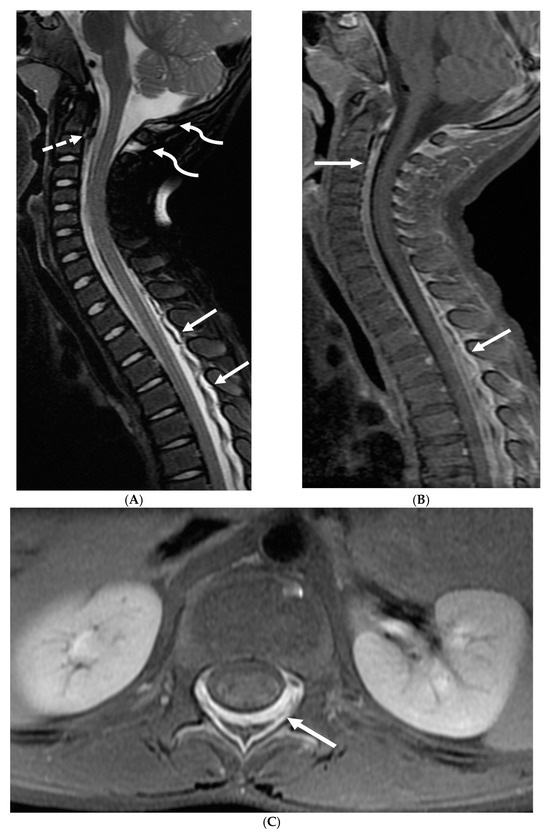

Prototheca species are unicellular algae that are typically known to involve the cutaneous and subcutaneous tissues in humans [6]. Systemic involvement, although rare, can cause meningitis, peritonitis, endocarditis, etc. and is commonly seen in immunodeficient individuals [7]. Prototheca spp. infections are usually exogenous and associated with traumatic inoculation from contaminated soil or water. They can also occur from surgery or catheterization, and even insect bites [8]. Exposure leads to chronic granulomatous inflammation with necrosis [6]. Notably, diagnosis of protothecosis may be challenging as it is not easily identified on Hematoxylin and eosin (H&E) or routine fungal stains, and mimics many fungal infections such as Coccidiodes, Blastomyces. Imaging findings include diffuse LME along the cortical sulci and spinal cord, with multiple loculations given the chronic inflammatory response. These loculations characteristically cause mass effect leading to a flattened and deformed spinal cord (Figure 2) [9].

Figure 2.

Post contrast sagittal T1 brain (A), T1 spine (B), axial T1 brain (C) and spine (D): 17-year-old girl with couple of years of fatigue, shuffling gait, back/lower extremity pain. There is moderate ventriculomegaly (white star). Meningeal enhancement is present around the cervical cord (white arrow). Flattened and deformed brainstem & spinal cord diffusely (curved arrows) and enhancing septae (dashed arrows) within the thecal sac are noted likely from chronic meningitis. Basal cistern enhancement (open arrow) and septae (arrow head) in the lateral ventricles likely reflects sequela of chronic inflammation/infection. Pathology: Prototheca Zopfil.